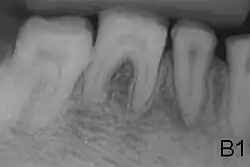

- Enamel of abnormal thickness due to malfunction in enamel matrix formation. Enamel is very thin but hard & translucent, and may have random pits & grooves. Condition is of autosomal dominant, autosomal recessive, or x-linked pattern. Enamel differs in appearance from dentine radiographically as normal functional enamel.[20]

- Enamel has sound thickness, with a pitted appearance. It is less hard compared to normal enamel, and are prone to rapid wear, although not as intense as Type 3 AI. Condition is of autosomal dominant, autosomal recessive, or x-linked pattern. Enamel appears to be comparable to dentine in its radiodensity on radiographs.

- Enamel defect due to malfunction of enamel calcification, therefore enamel is of normal thickness but is extremely brittle, with an opaque/chalky presentation. Teeth are prone to staining and rapid wear, exposing dentine. Condition is of autosomal dominant and autosomal recessive pattern. Enamel appears less radioopaque compared to dentine on radiographs.